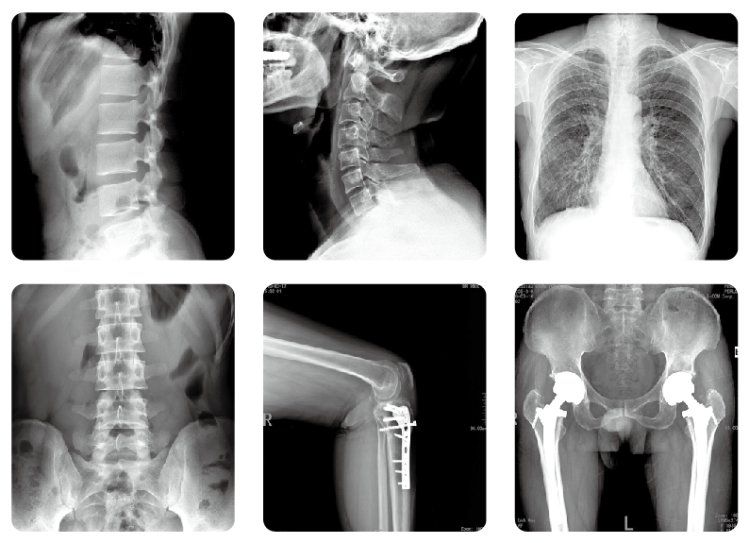

什么是鐮刀臂dr?鐮刀臂dr是一款擁有U型鐮刀臂的dr設(shè)備,簡稱dr,主要用于對人體胸腔、四肢、盆腔、腰椎等部位進行攝片檢查。它不同于傳統(tǒng)的膠片成像技術(shù),使醫(yī)用診斷X線機實現(xiàn)無膠片化,并可將數(shù)字圖像傳送至其他設(shè)備或網(wǎng)絡(luò)系統(tǒng)中去,開創(chuàng)了放射診斷新領(lǐng)域。

鐮刀臂dr的特點是穿過人體的X射線直接投射到平板式圖像探測器(簡稱DR板),然后應(yīng)用計算機技術(shù)將數(shù)字圖像采集、處理、運輸及顯示至監(jiān)視器上,供醫(yī)務(wù)人員觀察人體臟器組織的圖像,達到診斷的目的。